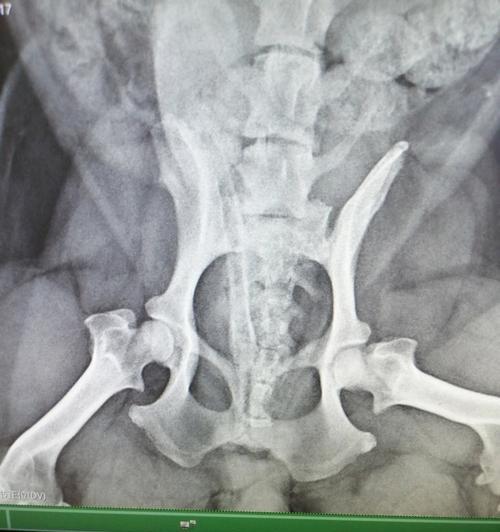

狗狗腿髋坏死(了解腿髋坏死的原因与治疗方法,为宠物狗的健康尽一份责任) 狗狗腿髋坏死严重影响宠物健康,主要表现为疼痛跛行。该病由股骨头缺血坏死引起,可通过早期发现、合理治疗有效改善。非手术治疗适合初期症状,严重情况下需进行骨科手术。预防重于治疗,注意饮食运动管理。康复期需精心护理,给予充足心理支持,确保最佳恢复... 养护知识 2026-03-01 04:40 浏览:736